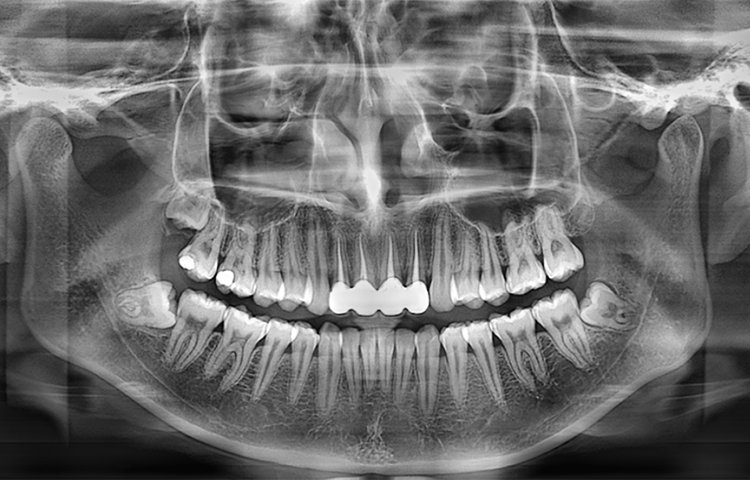

La máquina panorámica dental de Meyer proporciona a los dentistas imágenes panorámicas de alta calidad y vistas laterales, que pueden usarse para diagnosticar la dentición completa, la mandíbula y la articulación temporomandibular. También es adecuada para el diagnóstico de fracturas maxilofaciales y para el diseño de planes de ortodoncia.

Galería de imágenes